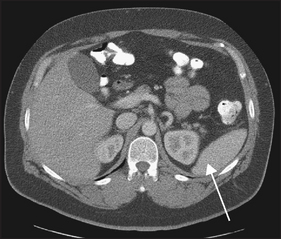

CT and ultrasound are often used to help determine the presence of splenomegaly or lymphadenopathy (see Figures 22.16 and 22.17).

Figure 22.16 CT scan of the abdomen. A normal-sized spleen is visible (arrow). (From Halpert RD. Gastrointestinal imaging: the requisites, 3rd edn. Mosby, 2006.)